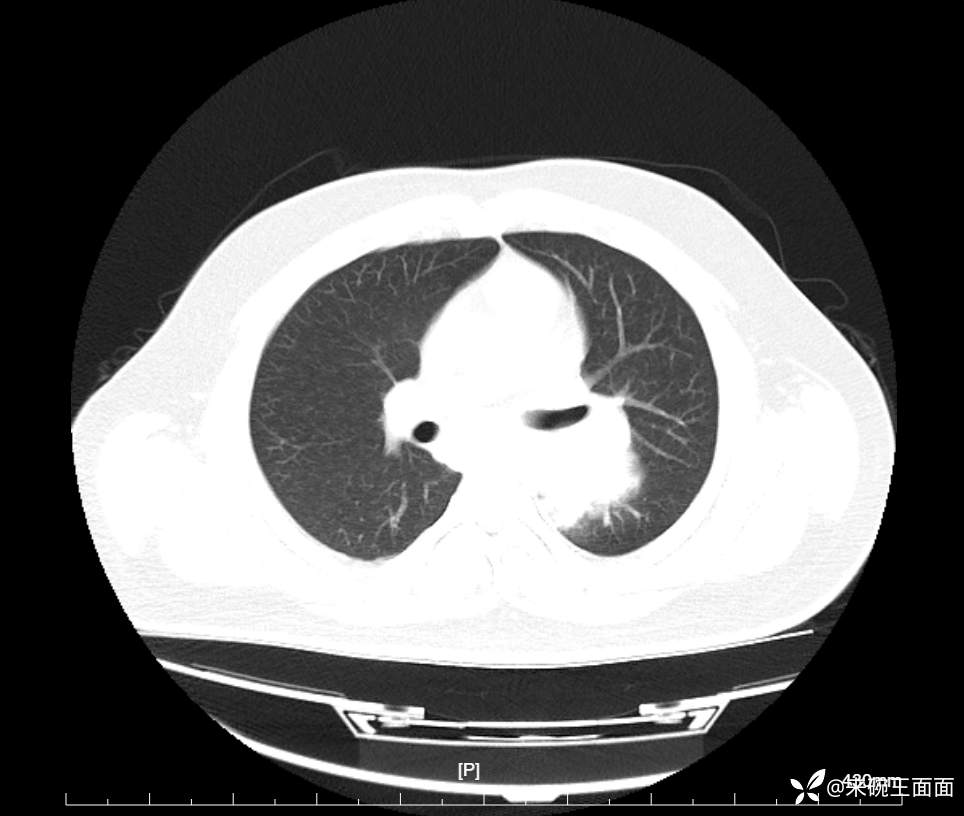

性别:男

年龄:27岁

主诉:胸闷胸痛数月余,休息后可自行缓解,无咯血症状。

个人史:数年吸烟史,具体不详。